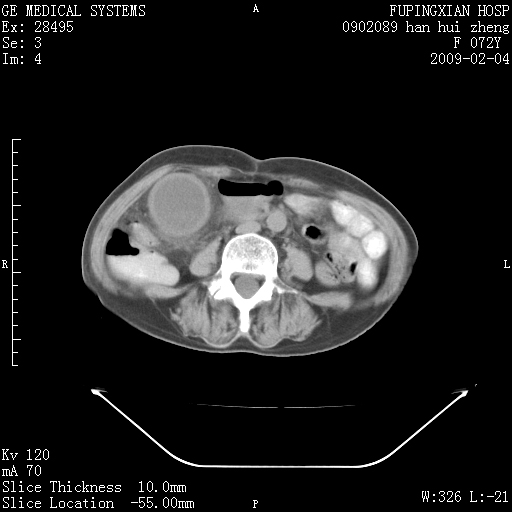

标题: CT17930:F72Y,右腹部包块5日,脐右扪及一包块,触痛。 [打印本页]

标题: CT17930:F72Y,右腹部包块5日,脐右扪及一包块,触痛。

胆囊增大,虽然内壁光滑,但囊壁不均匀性增厚,胆囊窝积液,所以首先考虑胆囊炎,但并不能排除胆囊癌的可能。诊断胆囊癌的依据是:胆囊壁呈不均匀性明显增厚,部分层面胆囊与肝脏界限不清。